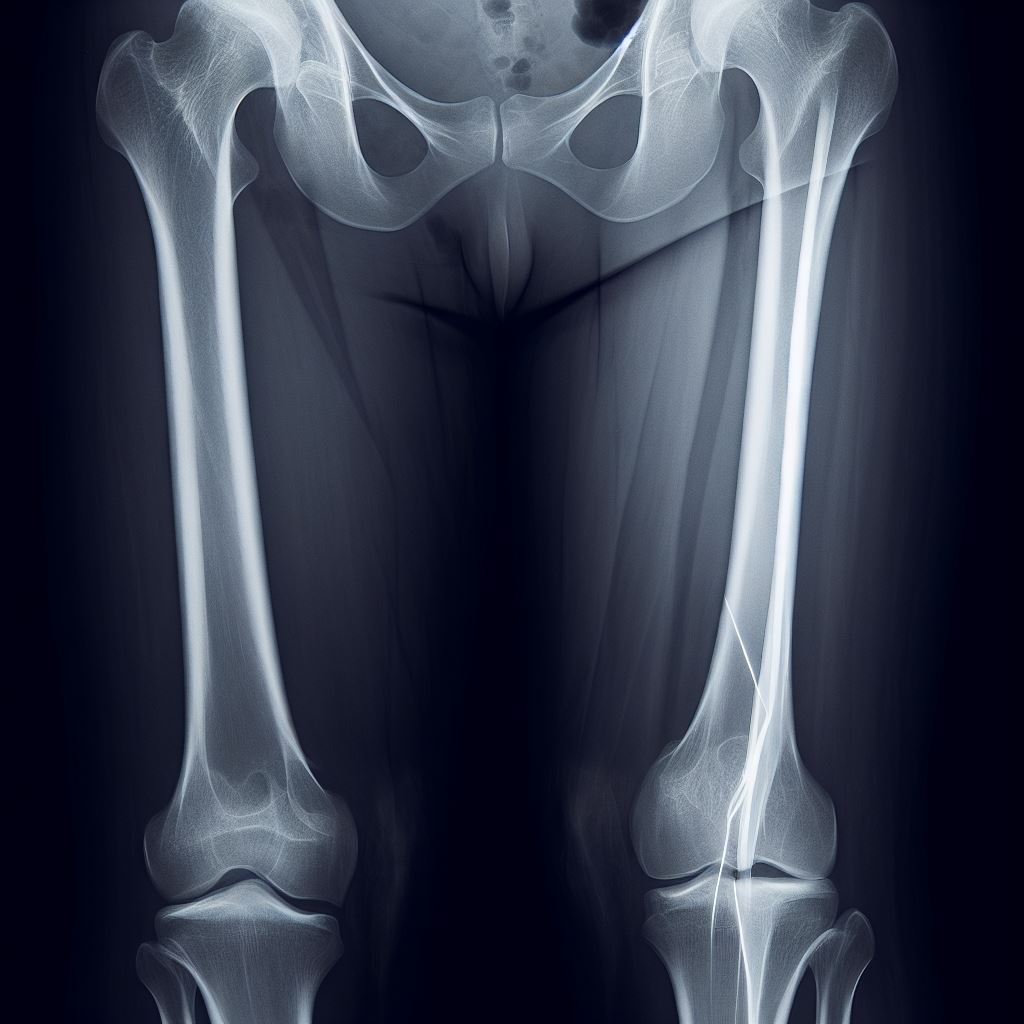

Atypical femoral fractures are rare complications that can arise from prolonged use of anti-resorptive osteoporosis treatments, such as bisphosphonates or denosumab. These fractures are characterized by a horizontal break in the femur that occurs without trauma, often preceded by thigh pain and frequently affecting both legs.

These fractures occur due to decreased metabolic turnover in the bone, making them similar to stress fractures. They predominantly affect females, likely due to different biomechanics stemming from pelvic and hip structure. Taking a break from treatment (a “drug holiday”) for a few years can reduce the risk of these fractures by 70%.

Treatment typically involves surgery to insert a metal rod in the femur, which can either treat a complete fracture or prevent an early fracture from becoming complete.